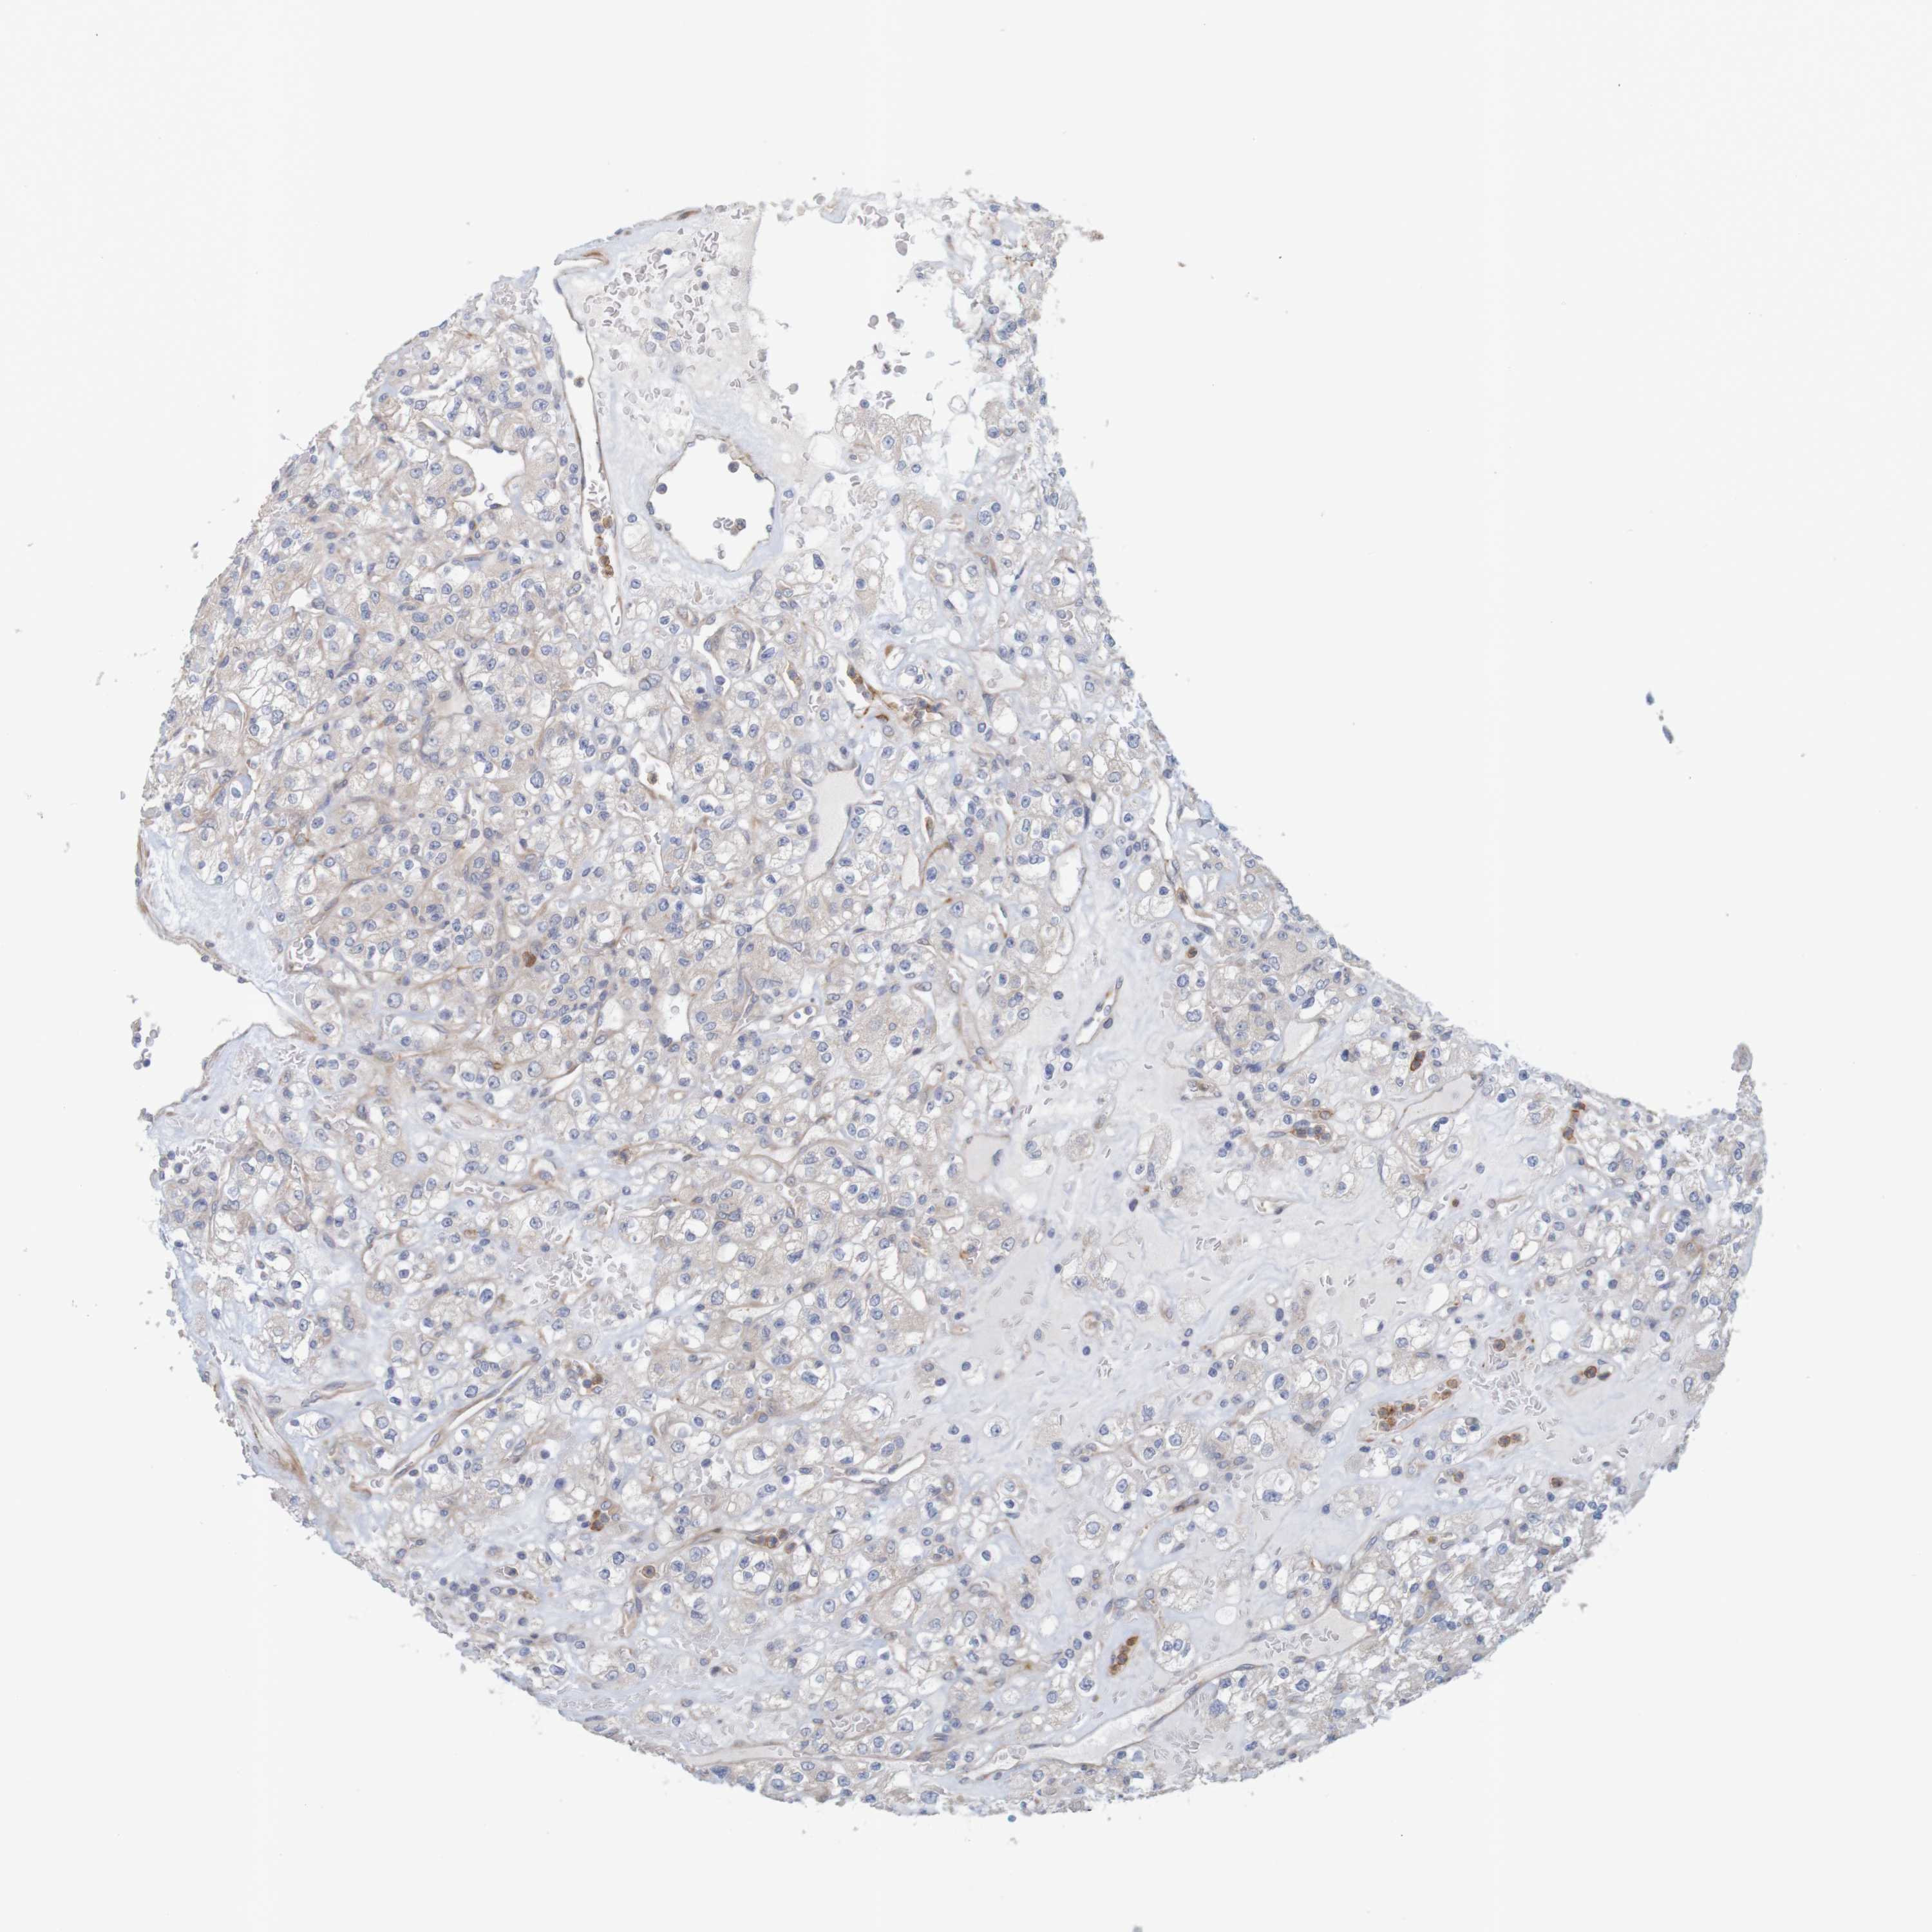

KIDNEY RENAL CLEAR CELL CARCINOMA (VALIDATION) - Interactive survival scatter ploti

The Survival Scatter plot shows the clinical status (i.e. dead or alive) for all individuals in the patient cohort, based on the same data that underlies the corresponding Kaplan-Meier plots. Patients that are alive at last time for follow-up are shown in blue and patients who have died during the study are shown in red.

The x-axis shows the expression levels (FPKM) of the investigated gene in the tumor tissue at the time of diagnosis. The y-axis shows the follow-up time after diagnosis (years). Both axes are complimented with kernel density curves demonstrating the data density over the axes. The top density plot shows the expression levels (FPKM) distribution among dead (red) and alive patients (blue). The right density plot shows the data density of the survived years of dead patients with high and low expression levels respectively, stratified using the cutoff indicated by the vertical dashed line through the Survival Scatter plot. This cutoff is automatically defined based on the FPKM cutoff that minimizes the p-score. The cutoff can be changed by dragging the vertical line or by entering a cutoff value in the square labeled "Current cut-off".

Under the Survival Scatter plot the p-score landscape (black curve; left axis) is shown together with dead median separation (red curve; right axis). Dead median separation is the difference in median mRNA expression between patients who have died with high and low expression, respectively. It is calculated as follows: median FPKM expression of dead patients with high expression - median FPKM expression of dead patients with low expression. This is intended to aid the user in visually exploring custom cutoffs and the associated p-scores and dead median separation.

Individual patient data is displayed and can be filtered by clicking on one or more of the category buttons on the top of the page. Categories describing expression level and patient information include: high, low, alive, dead, female, male and tumor stages. The scale of the x-axis can be toggled between linear and log-scale by clicking on the "x log" button. Mouse-over function shows TCGA ID, patient information and mRNA expression (FPKM) for each patient.

& Survival analysisi

Kaplan-Meier plots summarize results from analysis of correlation between mRNA expression level and patient survival. Patients were divided based on level of expression into one of the two groups "low" (under cut off) or "high" (over cut off). X-axis shows time for survival (years) and y-axis shows the probability of survival, where 1.0 corresponds to 100 percent.

KRT23 is not prognostic in Kidney Renal Clear Cell Carcinoma (validation)

TCGA RNA samplesi

RNA-seq data is reported as average FPKM (number Fragments Per Kilobase of exon per Million reads), generated by the The Cancer Genome Atlas (TCGA) .

Normal distribution across the dataset is visualized with box plots, shown as median and 25th and 75th percentiles. Points are displayed as outliers if they are above or below 1.5 times the interquartile range. FPKM values of the individual samples are presented next to the box plot.

Average pTPM 0.5

Number of samples 100